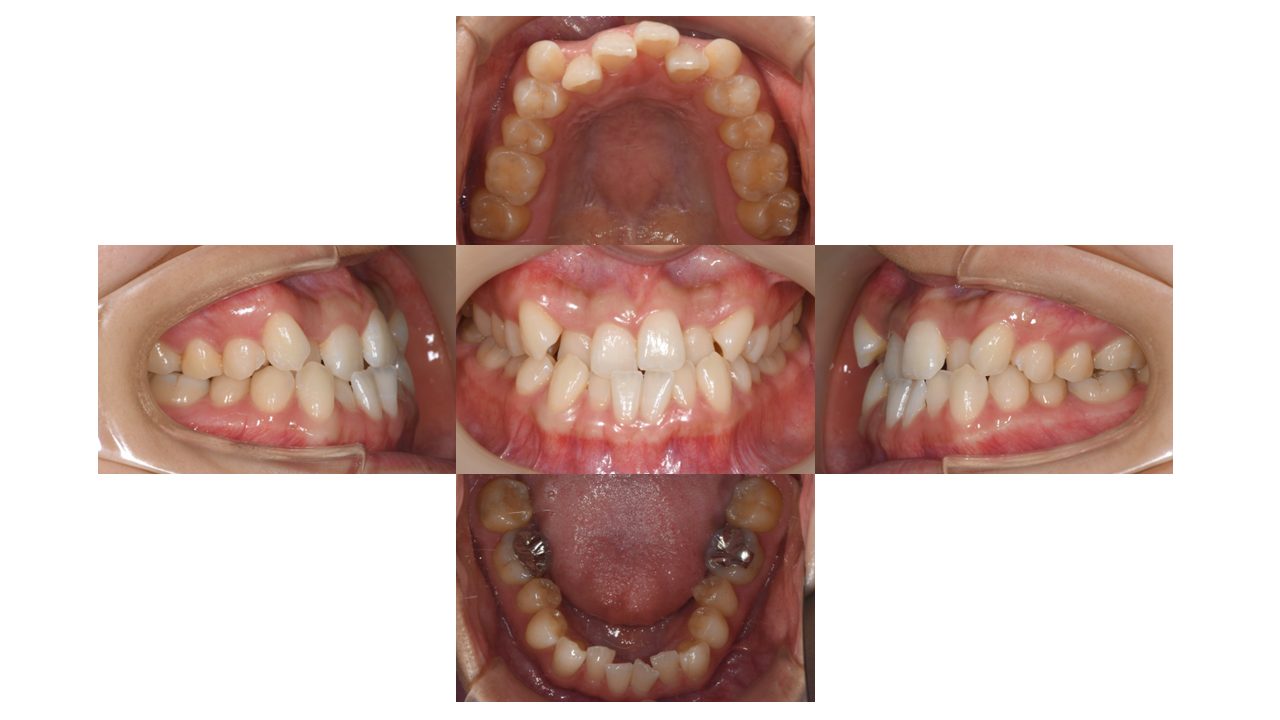

初診時の口腔内の状態です。

上下の凸凹・噛み合わせが悪いことにお悩みでご来院されました。